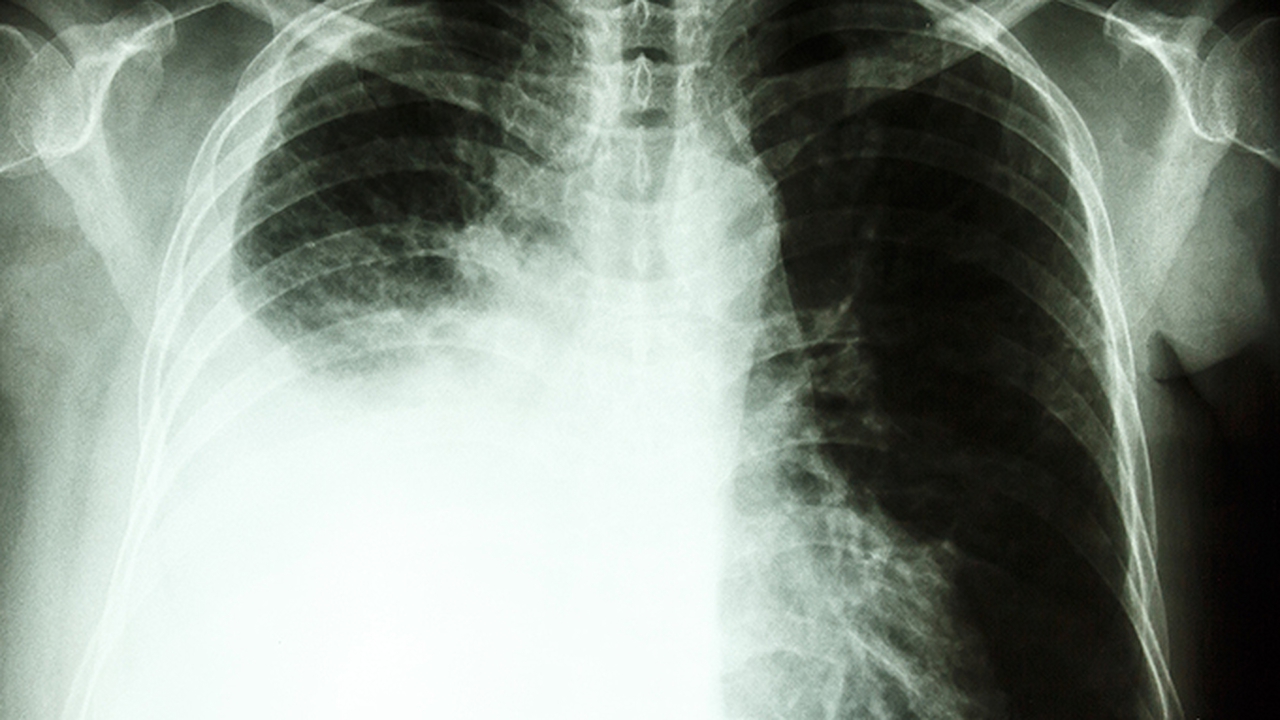

慢阻肺是一种常见的慢性呼吸系统疾病,主要由长期吸烟、空气污染等因素引起,表现为持续性气流受限。早期诊断和规范治疗对控制病情进展至关重要。

四川大学华西医院呼吸与危重症医学科是国家重点学科,在慢阻肺诊疗方面处于国内水平。科室拥有多位知名呼吸病学专家,开展肺功能检查、支气管镜检查等多项特色诊疗技术,为慢阻肺患者提供个性化治疗方案。

四川省人民医院呼吸与危重症医学科是四川省重点学科,在慢阻肺的规范化诊疗方面具有丰富经验。科室配备有的肺功能检测设备和呼吸康复设施,开展慢阻肺的早期筛查、诊断和长期管理。